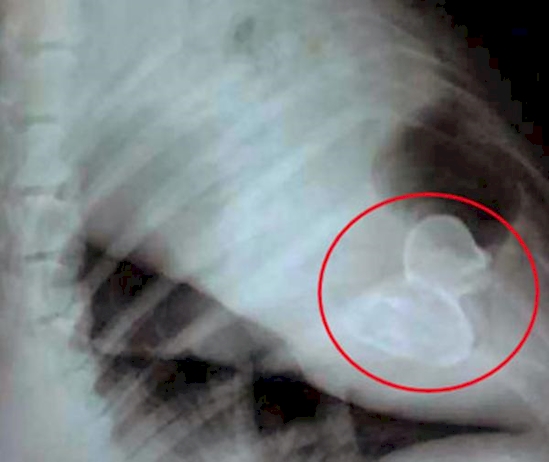

There are things that can be explained and there are things that cannot be explained.These 15 photos are going to be a challenge to make sense of.